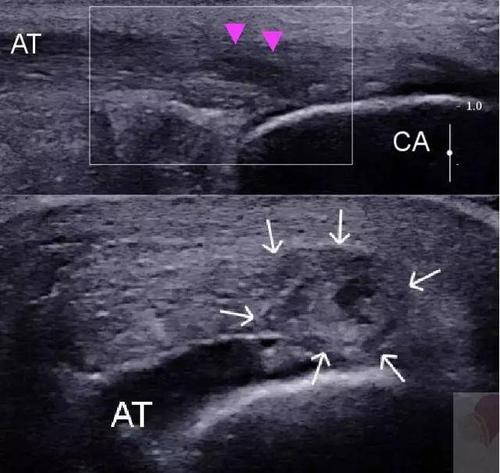

曾经有一个住院医师问我,王老师,跟腱断裂做核磁是诊断金标准我也知道,但是急诊没有核磁共振怎么办?我告诉她,如果没有核磁,我们可以使用B超检查,同样能诊断出跟腱断裂,而且更方便快捷,只是没有核磁共振更直观而已。如下图:

跟腱断裂B超检查